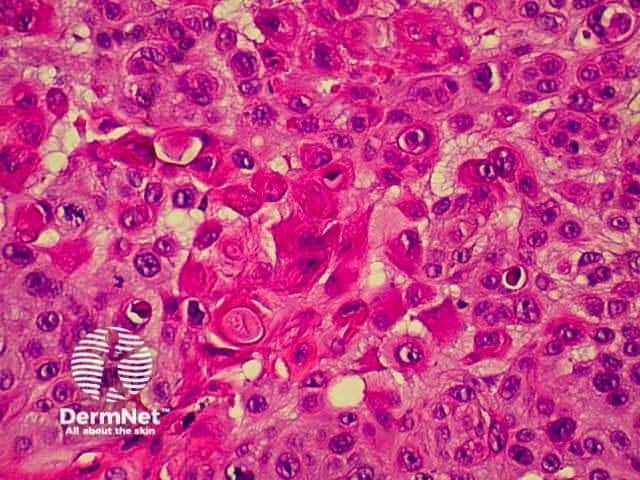

SCC is characterised by proliferation of irregular nests of abnormal squamous cells arising from the epidermis and invading the dermis. Tumours are traditionally divided into well, moderately or poorly differentiated tumours by a subjective assessment of how significantly the tumour cells differ from normal keratinocytes. In general, the greater the degree of keratinization, the better differentiated the tumour is thought to be. Except in the case of very poorly differentiated tumours, this does not have a great bearing on prognosis. More important is the depth and irregularity of invasion, particularly the presence of perineural infiltration, which is associated with a much higher rate of recurrence if not widely excised. The site of the lesion is also important; tumours of the lips and ears have a considerably higher rate of metastasis to lymph nodes.

From the above comments it can be seen that the histological features of SCCs can vary, but in general are:

Pathology of SCC Pathology of SCC Pathology of SCC Pathology of SCC